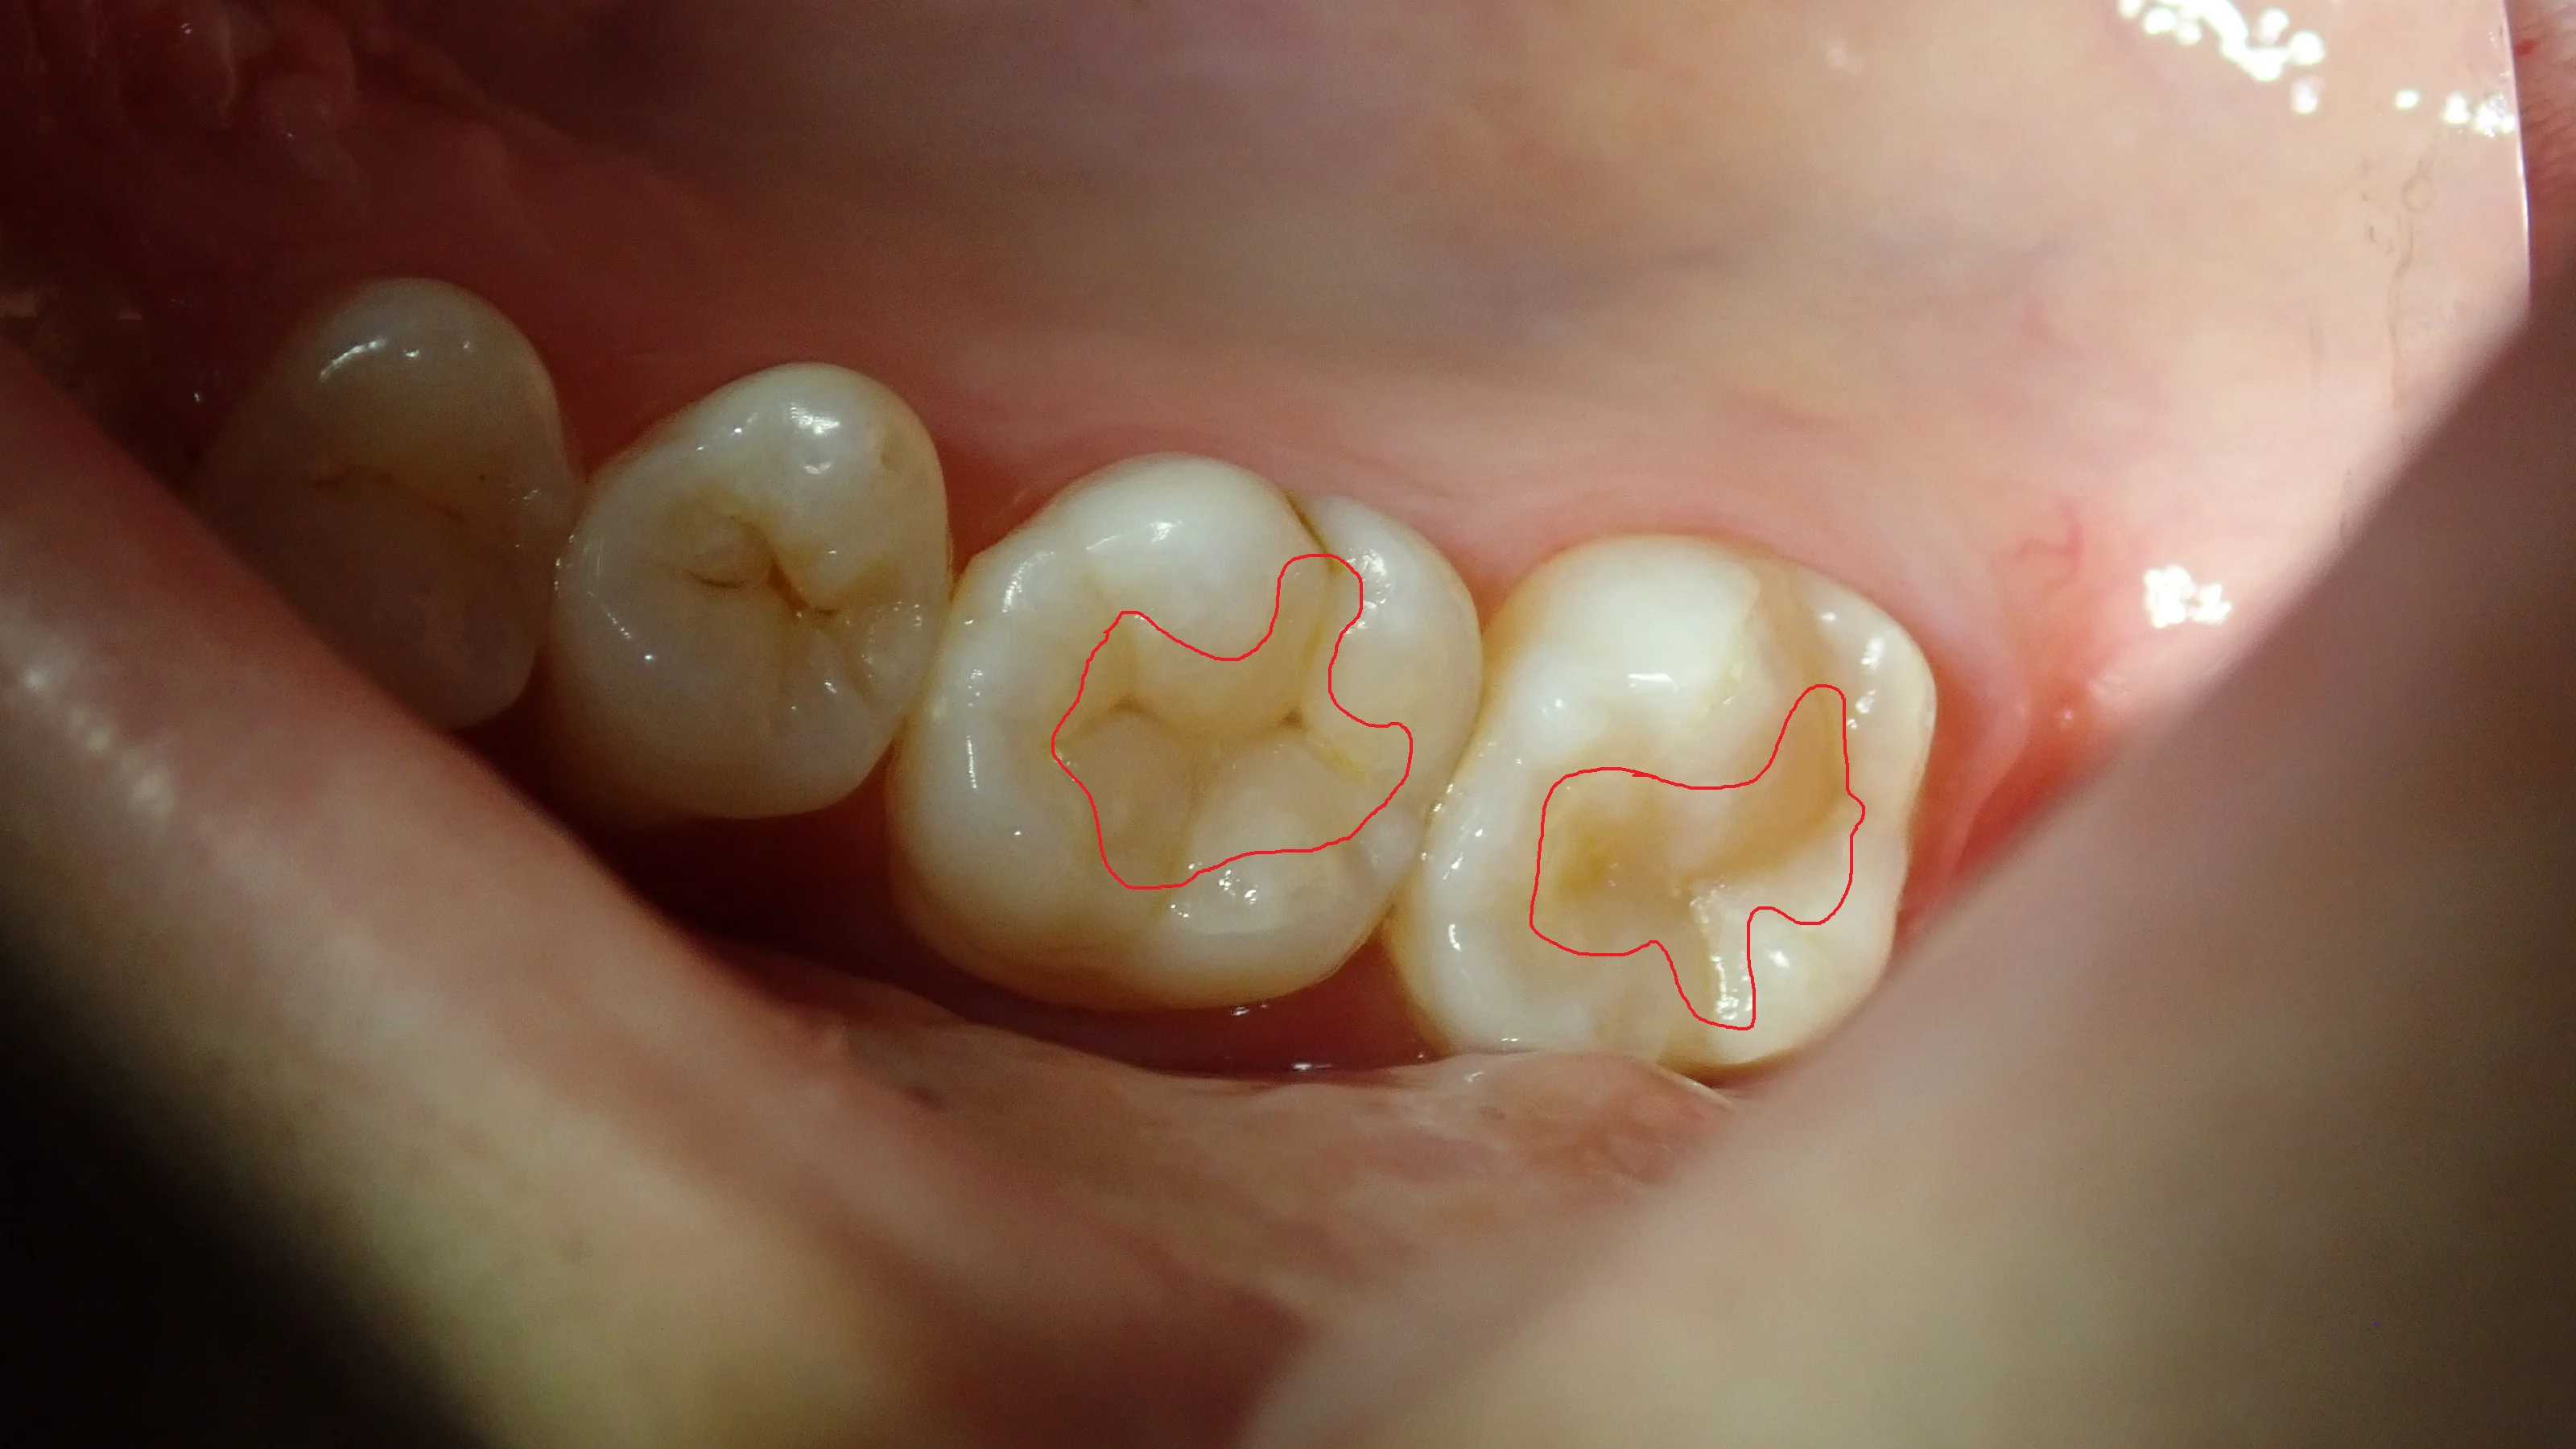

こちらがダイレクトボンディングから3年経過後の状態です。

一応詰めているところを赤い線で表すと、

こうなります。

手前の歯の着色などを考えるともう少し濃いめにステインを入れても良かった気がします。

今回の方も、幸い神経の温存も成功しているようで、ダイレクトボンディング自体も欠けたりもせずに順調に使用できているようで良かったです。